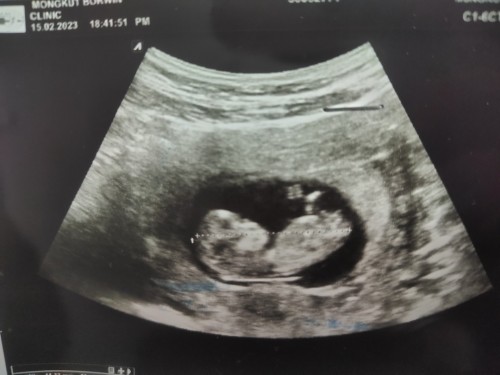

เดาเพศลูก ช หรือ ญ?

แม่ๆพอดูออกมั้ยคะ ว่า ช หรือ ญ หมอบอกเหมือน ช แต่ รอ ประมาณ 20w+ ถึงคอนเฟิมอีกทีค่ะ

อันนี้คือกี่วีคค่ะ ของเรา 11วีค หมอบอกเห็นช้างน้อยชัดเลยน่าจะเป็นผู้ชาย แต่เรารอดูให้ชัวร์เหมือนกันค่ะ

ในรูปคือด้านข้างมองไม่เห็นเพศค่ะ

ในภาพน้องกี่วีคแล้วคะ

11w ค่ะ